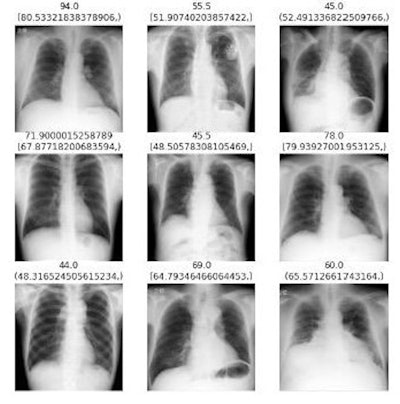

In this study, the researchers aimed to develop a convolutional neural network (CNN) model that could potentially assess height and weight based on chest x-rays. They used 6,453 x-rays from male patients and 7,879 x-rays from female patients to train and test the model, with height and weight data extracted from electronic medical records, then applied an image regression model (ResNet-152) that previously has been reported to predict age from CT imaging data. For input, they prepared linked datasets in which the CNN associated the x-rays with height and weight.

According to the findings, the correlations between the model's predicted values and actual values for males and females were 0.855 and 0.81, while the correlation coefficients for weight for males and females were 0.793 and 0.86.